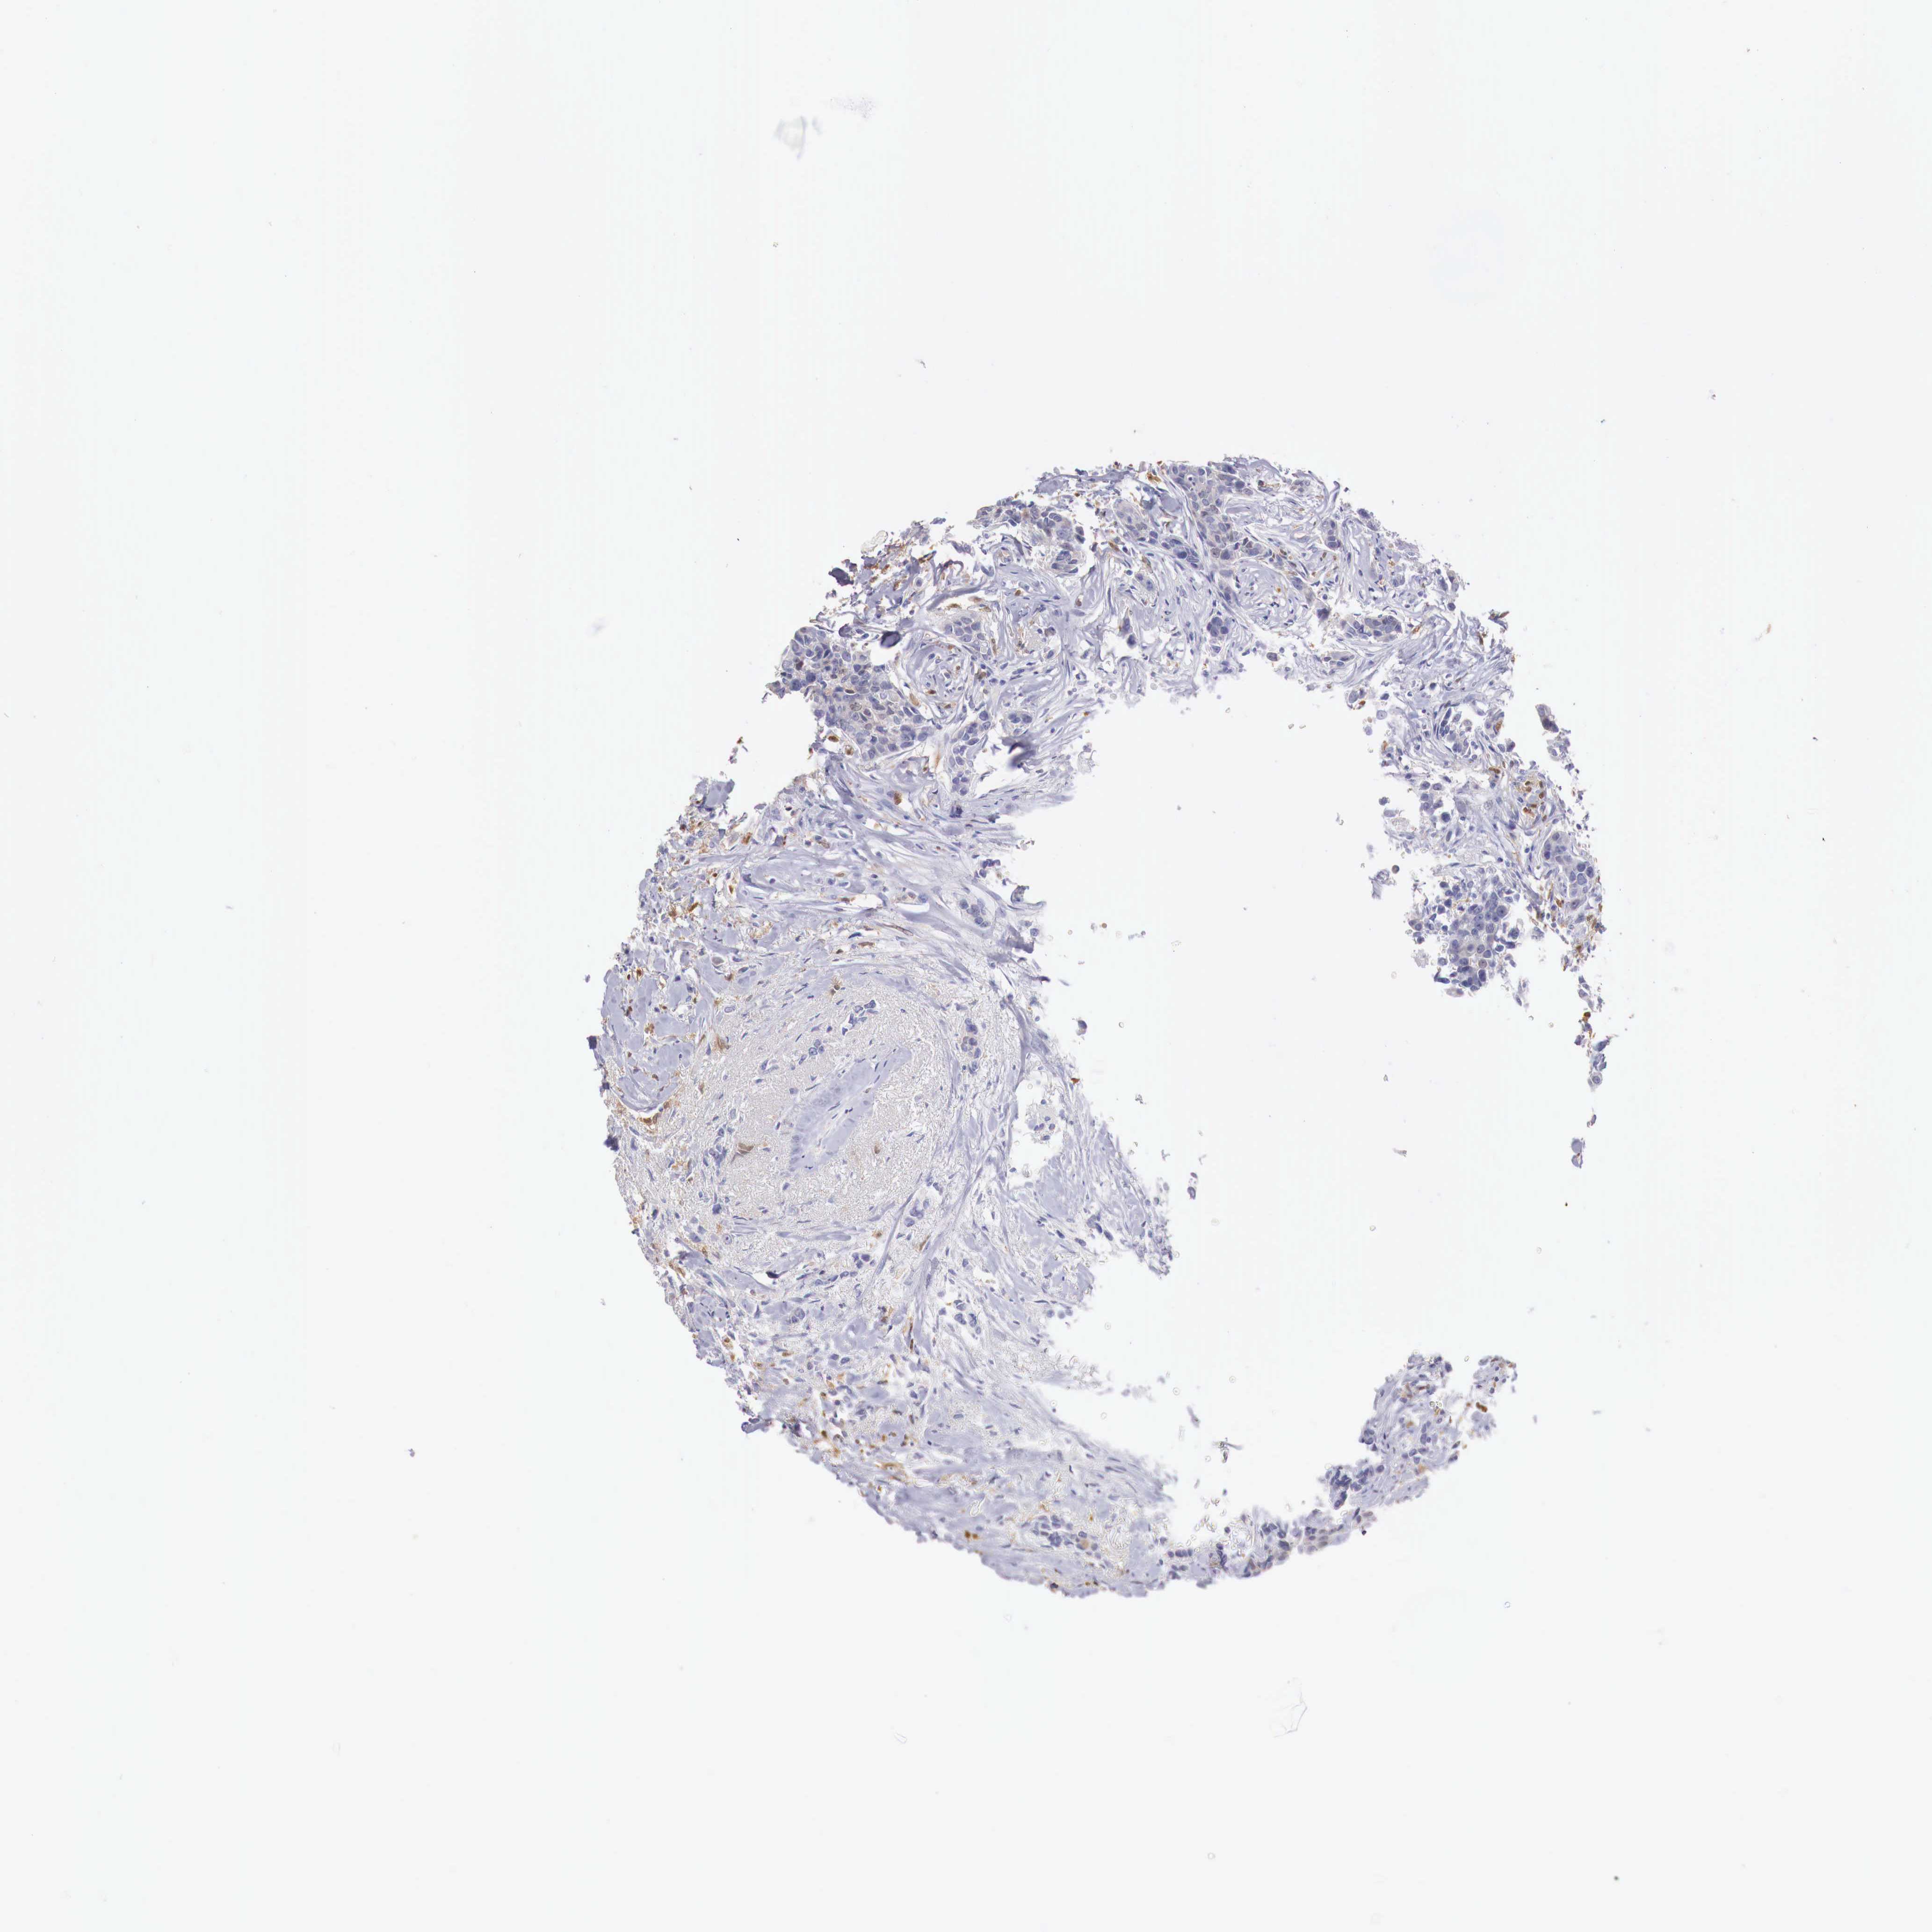

CANCER BREAST CANCER Show tissue menu

BRCA TCGA BRCA VALIDATION PROTEIN EXPRESSION